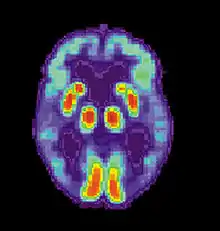

Аппаратура SPECT- и PET-визуализации при её доступности может быть использована для подтверждения диагноза совместно с другими методами оценки, включающими анализ ментального статуса[128]. У людей, уже страдающих от деменции, SPECT, по некоторым данным, позволяет более эффективно дифференцировать болезнь Альцгеймера от других причин, по сравнению со стандартным тестированием и рассмотрением анамнеза[129]. Возможность наблюдать отложения бета-амилоида в мозге живых людей появилась благодаря созданию в Питтсбургском университете Питтсбургского состава B (PiB), связывающегося с амилоидными отложениями при введении в организм. Короткоживущий радиоактивный изотоп углерод-11 в соединении позволяет определять распределение этого вещества в организме и получать картину амилоидных отложений в мозге больного с помощью ПЭТ-сканера[130]. Показано также, что объективным маркером болезни может быть содержание бета-амилоида либо тау-белка в спинномозговой жидкости[131]. Эти два новых метода вызвали предложения о разработке новых диагностических критериев[115][121]. Другие препараты для PET-визуализации: флорбетапир, флутеметамол, флорбетабен, флортауципир.